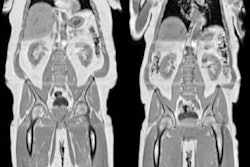

Body composition analysis on CT exams can identify ovarian cancer patients who are more likely to have complications related to chemotherapy, according to research presented at ECR 2022 Overture.

In a retrospective study involving 69 ovarian cancer patients, a team of researchers led by Dr. Stefania Rizzo of the Imaging Institute of Italian Switzerland in Lugano, Switzerland found statistically significant associations for three CT body composition measures with chemotoxicity from neoadjuvant chemotherapy. This information could then be used clinically to adjust chemotherapy doses and to enable interventions such as recommending exercise and nutritional adjustments prior to surgery.

Using version 5.0 of the Slice-O-Matic software (Tomovision), the researchers extracted skeletal muscle area, skeletal muscle density, subcutaneous adipose tissue, and visceral adipose tissue data from an axial CT image at the level of the L3 vertebrae.